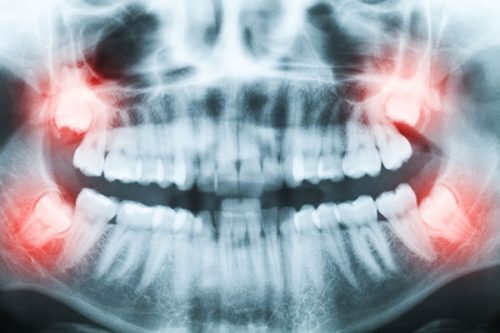

For simple wisdom teeth extractions, you may not need or want to be fully sedated. If you have impacted wisdom teeth, heavier sedation — like general anesthesia — may be recommended. We’ll help you understand exactly what to expect and can work around your needs.